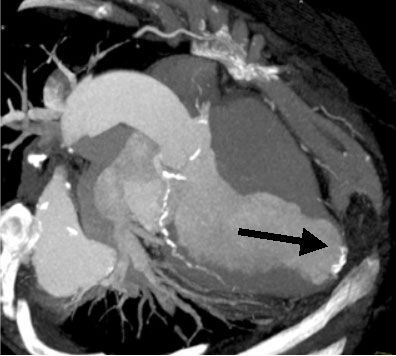

4. состояния после перенесенных после операций аорто - коронарного шунтирования (АКШ) или чрезкожной транслюминальной ангиопластики коронарных артерий (ЧТКА) с имплантацией стентов для определения состоятельности аорто - коронарных шунтов или внутрисосудистых эндопротезов [7,8] (рис.№ 4).

![]() |

| Рис.4. 3-D реконструкция у пациента после АКШ и ЧТКА со стентированием. Рисунок слева: стрелками отмечены аорто - коронарные шунты. Рисунок справа: стеноз проксимального сегмента коронарной артерии и ниже - функционирующий стент.

|